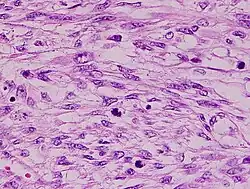

The tumors are usually hemorrhagic and soft and microscopically marked by pleomorphism, abundant (15–30 per 10 high-power fields) abnormal mitotic figures, and coagulative tumor cell necrosis. The differential diagnosis, which includes spindle cell carcinoma, spindle cell melanoma, fibrosarcoma, malignant peripheral nerve sheath tumor and even biphenotypic sinonasal sarcoma, is wide.